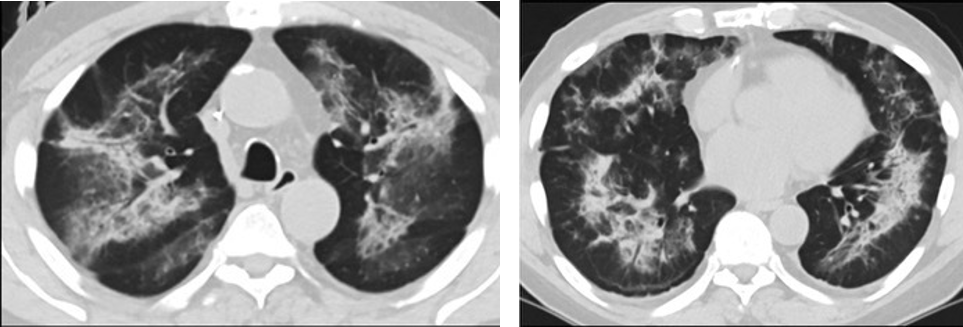

疑点一,电子烟患者的CT影像和临床表现并不具有特异性。所谓美国电子烟肺炎患者,其实是对没有其他合理诊断证据、吸食电子烟肺炎患者的统称。这些患者在病发前90天内吸食了电子烟,尤其值得注意的是,部分患者的CT影像特征和临床表现与病毒性肺炎患者极其相似。

同一病人CT影像显示,中、下肺轴位CT平扫显示毛玻璃样混浊伴胸膜下保留(箭头)疑点二,中国科研工作者从60篇研究论文中筛选出142位电子烟肺炎患者的250张影像图片,邀请3位放射科权威专家,对上述全部影像图片、相关病人临床信息以及文献原文进行了仔细全面研究与审查,发现:16位被文献报道为电子烟肺炎的患者被专家判定为“病毒性感染”,即有可能是新冠肺炎的“疑诊患者”,其中更有5位临床症状和治疗情况相对完整的患者被判定为“中度可疑”。